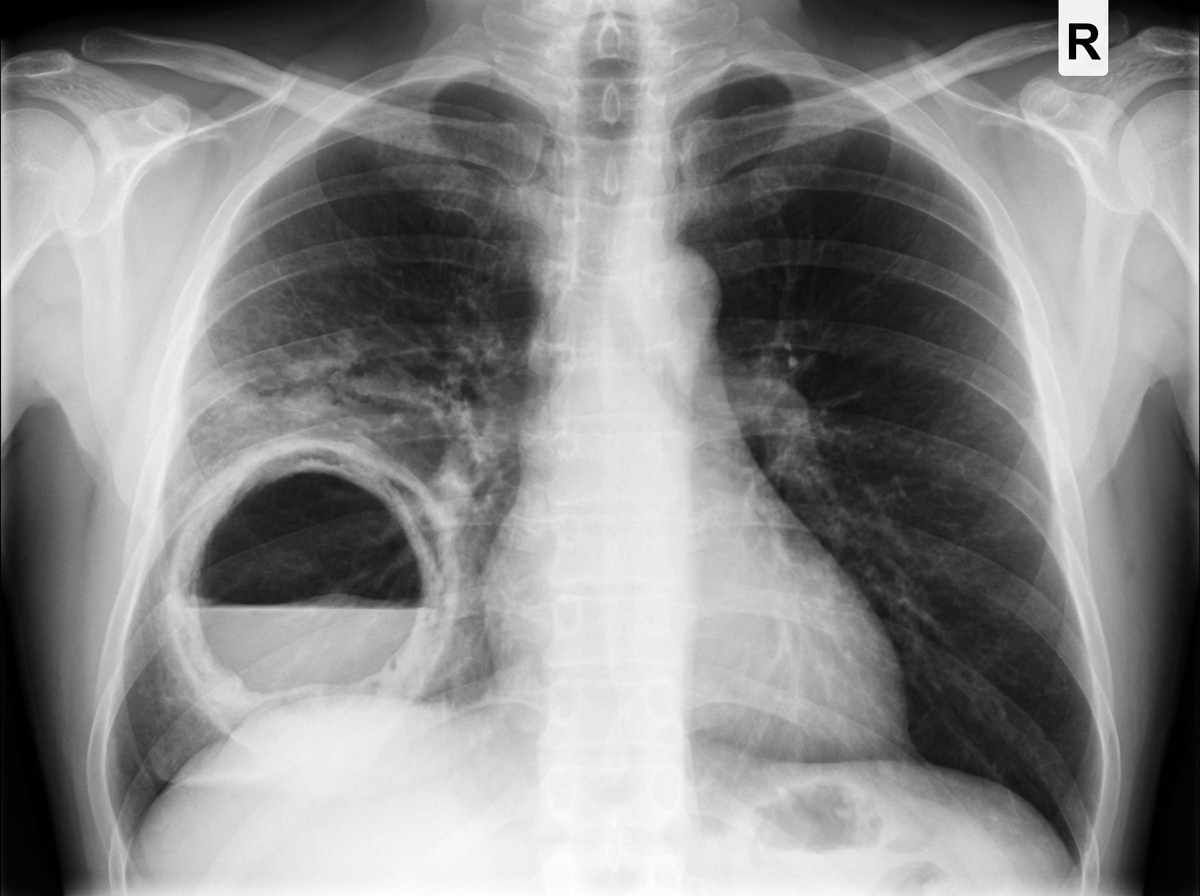

A 40-year-old man with a history of substance abuse and HIV infection presents with fever, weight loss, production of foul-smelling sputum, and shortness of breath for 2 weeks. Physical examination reveals tachypnea and clubbing of his digits. Lung auscultation demonstrates diffuse rhonchi and an area of egophony with whispering pectoriloquy in the right posterior chest. Arterial blood gases show a PaO2 of 59 mm Hg on room air. A chest X-ray is available. What is the most likely diagnosis?

Explanation: ***Correct: Lung abscess*** - The clinical hallmark here is **foul-smelling (putrid) sputum**, which strongly indicates **anaerobic bacterial infection** — the pathognomonic feature of a lung abscess - **Substance abuse** predisposes to **aspiration** (during intoxication/altered consciousness), seeding dependent lung segments (right lower lobe, posterior segments) with oral anaerobes (e.g., *Bacteroides*, *Peptostreptococcus*, *Fusobacterium*) - **Digital clubbing** indicates a chronic suppurative pulmonary process - **Egophony and whispering pectoriloquy** in the right posterior chest reflect surrounding consolidation/inflammation adjacent to the cavity - The chest X-ray characteristically shows a **thick-walled cavitary lesion with an air-fluid level**, most commonly in the right lower lobe or posterior segment *Incorrect: Pneumococcal pneumonia* - *Streptococcus pneumoniae* is an aerobe — it does **not** produce foul-smelling (putrid) sputum - Presents as lobar consolidation without cavitation or air-fluid levels on chest X-ray - Does not cause digital clubbing in an acute 2-week course *Incorrect: Pneumocystis pneumonia (PCP)* - Common opportunistic infection in HIV-positive patients, but classically presents with **dry, non-productive cough** and bilateral perihilar **ground-glass opacities** (interstitial pattern) on imaging - PCP does **not** produce foul-smelling sputum and does not form cavities or air-fluid levels - LDH is typically elevated; induced sputum/BAL is needed for diagnosis *Incorrect: Squamous cell carcinoma* - While squamous cell carcinoma can cavitate, it typically presents over **months to years** — not an acute 2-week febrile illness - Does not produce foul-smelling sputum acutely - Less likely in the clinical context of aspiration risk with acute infectious symptoms